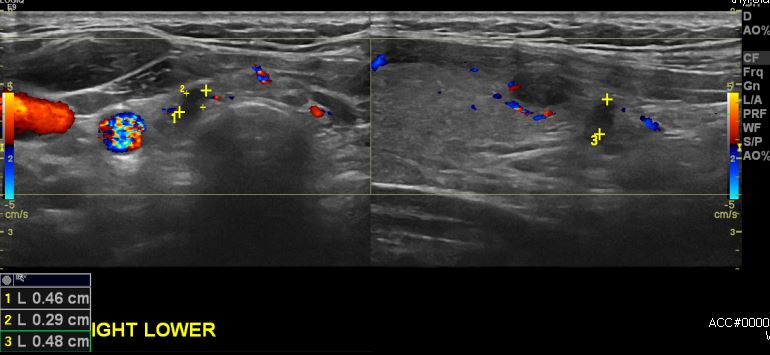

상기환자 갑상선의 이상소견으로 본원 내원하시여 본원 3개월 추적관찰하신 30대 여성분으로  우측 갑상선 하부 으심스러운 혹 세침검사 시행하여 우측 갑상선 유두암 진단

되었습니다.